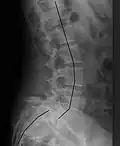

X-ray of the lateral lumbar spine with a grade III anterolisthesis at the L5-S1 level

X-ray of a grade 4 anterolisthesis at L5-S1 with spinal misalignment indicated